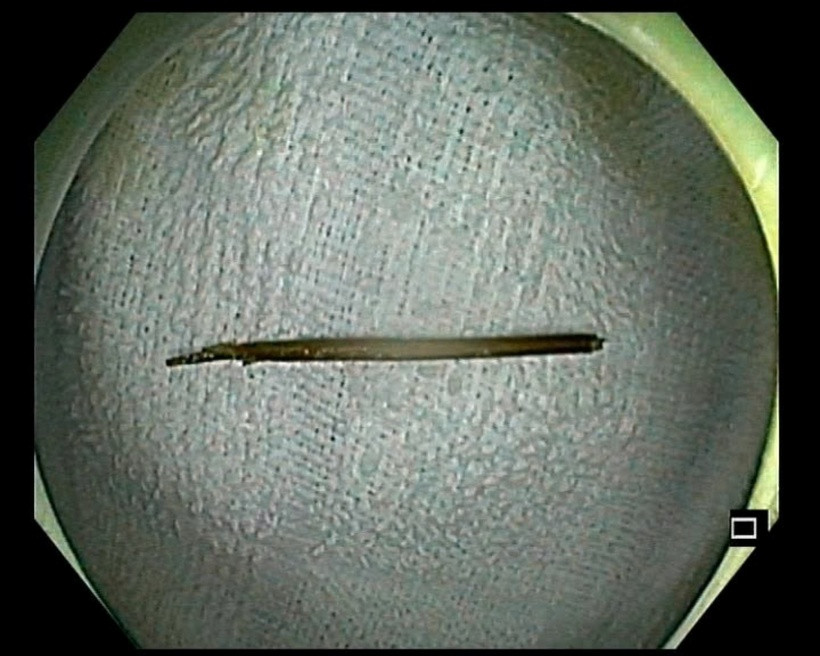

Chiếc tăm nhọn dài 6cm được lấy ra khỏi cơ thể bệnh nhân. Ảnh: Báo Công lý.

Trong quá trình nội soi, các bác sĩ Khoa Thăm dò chức năng phát hiện một chiếc tăm tre dài khoảng 6cm đã xuyên thủng thành đại tràng, gây viêm nhiễm tại chỗ – một tình trạng nguy hiểm có thể dẫn đến viêm phúc mạc, thủng ruột và nhiều biến chứng nghiêm trọng nếu không được phát hiện và xử trí kịp thời.